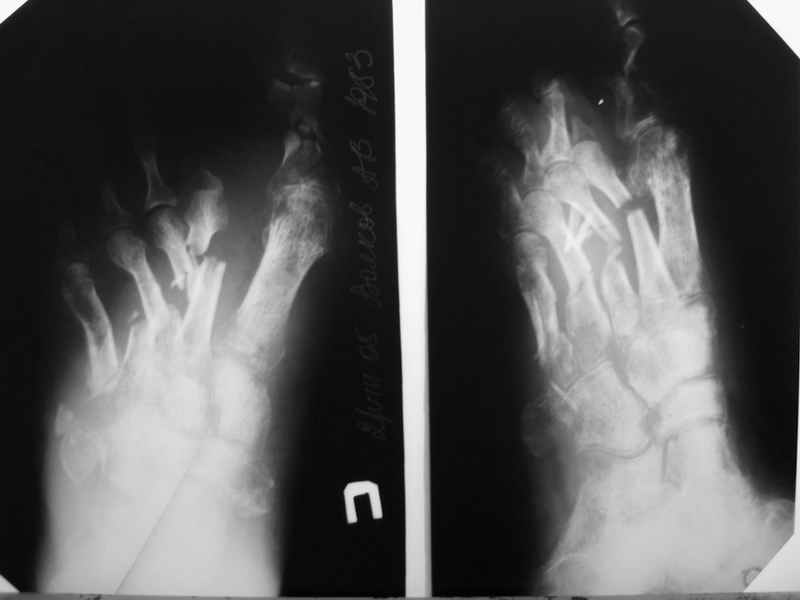

В продолжение темы конкретного больного. К сожалению, после достаточно длительной ходьбы несколько дней назад, появились классические признаки воспаления. Сегодня выполнил некрэктомию-дистальный отломок 2 плюсневой кости с остатком фрагмента основной фаланги- буквально плавали в гное. Рану тампонировал с левосином. Компенсации кровооброщения не наступило?

P.S. Перед операцией взял посев и на чувствительность, но ответ(в нашей лаборатории) скорее всего предсказуем-Staph aures. Посмотрим на чувствительность.

Здравствуйте Алексей, сожалею о продолжении воспалительного процесса, да видать спицевой остемиелит лечить придется долго. После купирования гнойного процесса через Департамент здравоохранения можно положить больного к нам в клинику. ( вы пишете бумагу в департамент, что мол больному показано лечение в ГКБ 64 и он сам или его родные получают такой красный талон на госпитализацию)

но я вот о чем подумываю, не пора ли подумать об ампутации? остемиелит можно лечит долго, любые железки будут выгнаиваться...

Здравствуйте, Тимур Вячеславович. Спасибо за живой интерес к проблеме: этапы к Вам понял. Насчет ампутации, я думаю, что больной еще не созрел, наоборот- полон оптимизма. Вот свежие рентгенограммы и стопа на 5 день после операции. Появились грануляции, но рана глубокая- 2-2,5 см. Хотелось бы узнать о Вашей тактике на ближайший период, если это возможно. С уважением, Алексей